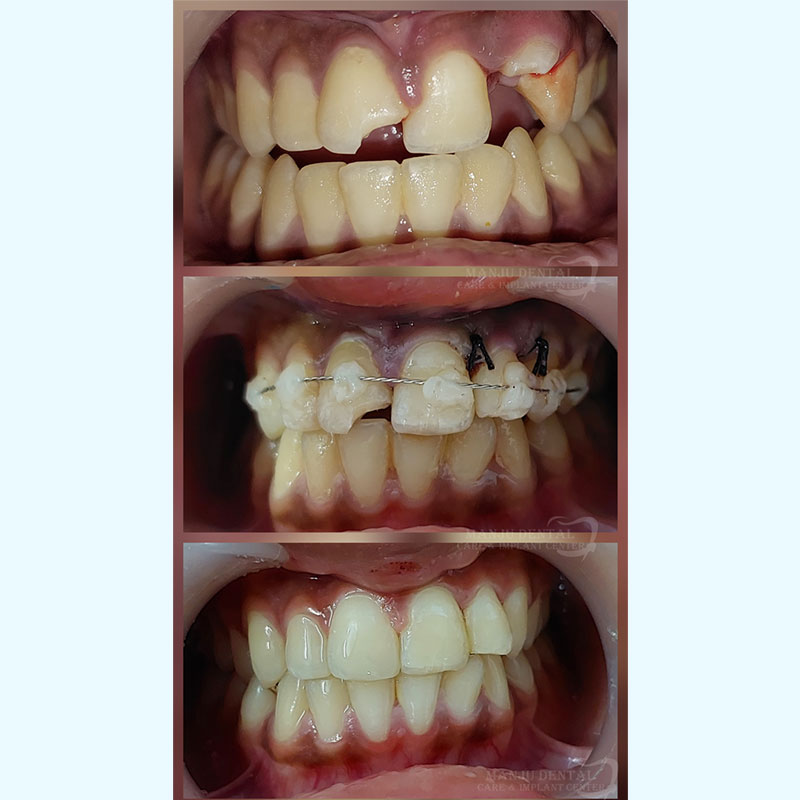

Comprehensive Dental Trauma Management